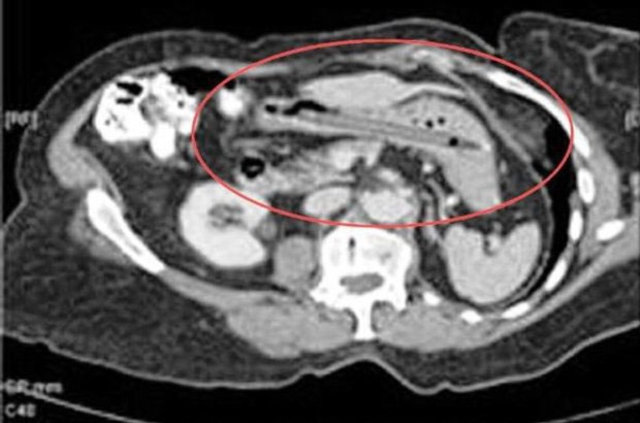

Genellikle yabancı cisimler 'X' ışınıyla görülebilir. Direk grafi ile metal ve 'X' ışınına duyarlı cisimleri rahatlıkla görebiliyoruz. Ama plastikleri göremiyoruz. Bu durumda oyuncağın bir parçasıyla yutulan parçayı anlamaya çalışıyoruz."

Hastaneye yabancı cisim yutma şikayetiyle getirilen çocuğun ilk etapta takip edildiğini, yaşına ve yuttuğu objenin özelliğine göre de müdahaleye karar verildiğini belirten Dr. Miray Karakoyun, yabancı cisim yutma şikayetiyle başvuran hastalarda, yabancı cismin ne olduğu, çocuğun kaç yaşında olduğu ve yutulan maddenin çekilen filmi sonucu sistemin neresinde olduğunun kendileri için önemli olduğunu kaydederek şöyle dedi:

Bir diğer sık karşılaştığımız durum ise pil yutmaları, bunlar yakıcı olduğu için bekleme süresinde 48 saati geçirmemeye özen gösteriyoruz. Pilin vücutta bulunduğu yer de müdahale etme koşullarını değiştirebiliyor.

Son olarak 9 aylık bir bebek pil yutma şikayetiyle getirildi. Pilin midede olmasına rağmen, yeni olması ve bebeğin yaşının küçük olması nedeniyle 3 saat içinde müdahalemizi yaptık endoskopiyle pili çıkarttık. Buna rağmen midede yanıklar vardı, bir süre hastamızı takip ettikten sonra taburcu ettik." (DHA)